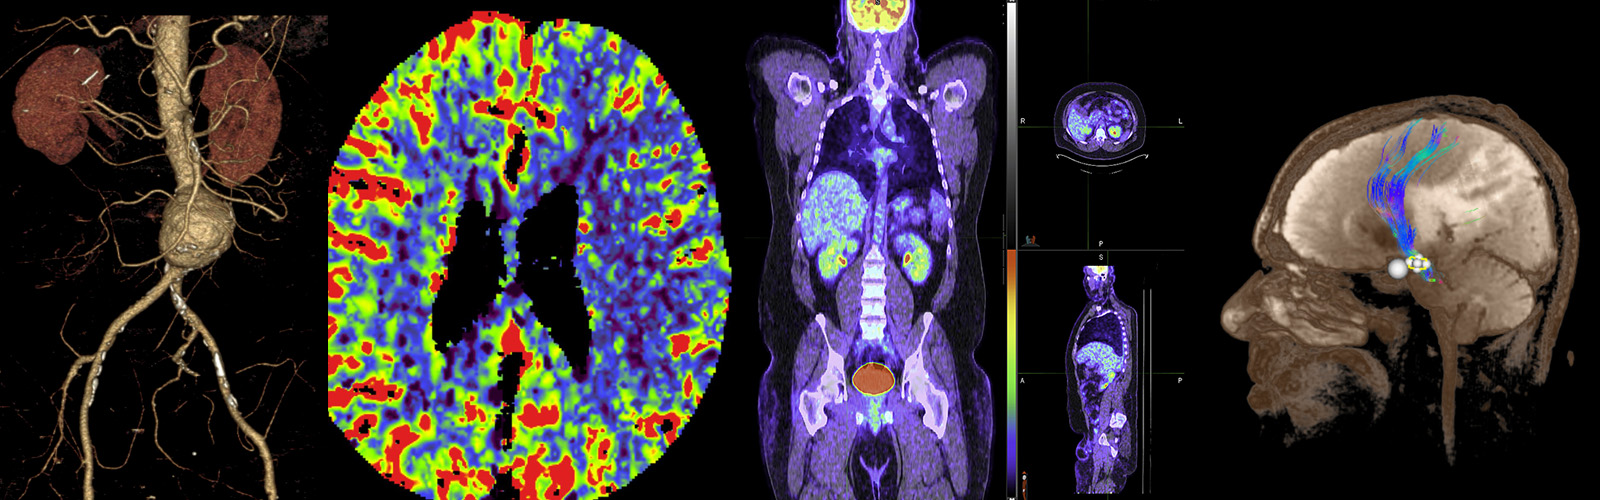

Radiology Research

Our mission is simple: to bring scientific advances in medical imaging to clinical application. Our current major areas of focus include Interventional Neuroradiology, Biomarker Development, Molecular Imaging, Nuclear Medicine Physics, and Cell Biology. Learn more.